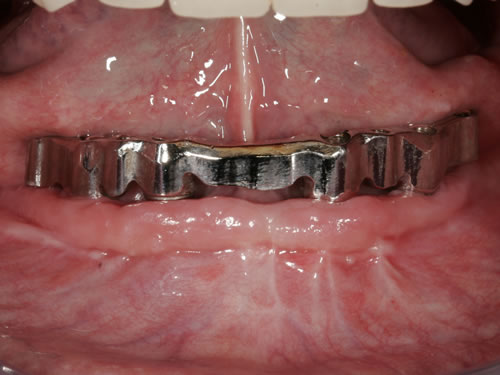

Abb. 3.7: Individuelle Stegversorgung aus Stahl auf vier Implantaten im zahnlosen Unterkiefer.

Abb. 3.8: Individuelle Stegversorgung aus Gold auf vier Implantaten im zahnlosen Unterkiefer.

Für den zahnlosen Ober- und Unterkiefer werden dies häufiger Stegkonstruktionen oder Teleskopversorgungen sein (Abb. 8.8 bis 8.16).

Abb. 8.8: Individueller Steg auf 4 Implantaten im zahnlosen Unterkiefer.

Abb. 8.10: Individueller Stahlsteg auf 4 Implantaten im zahnlosen Oberkiefer.